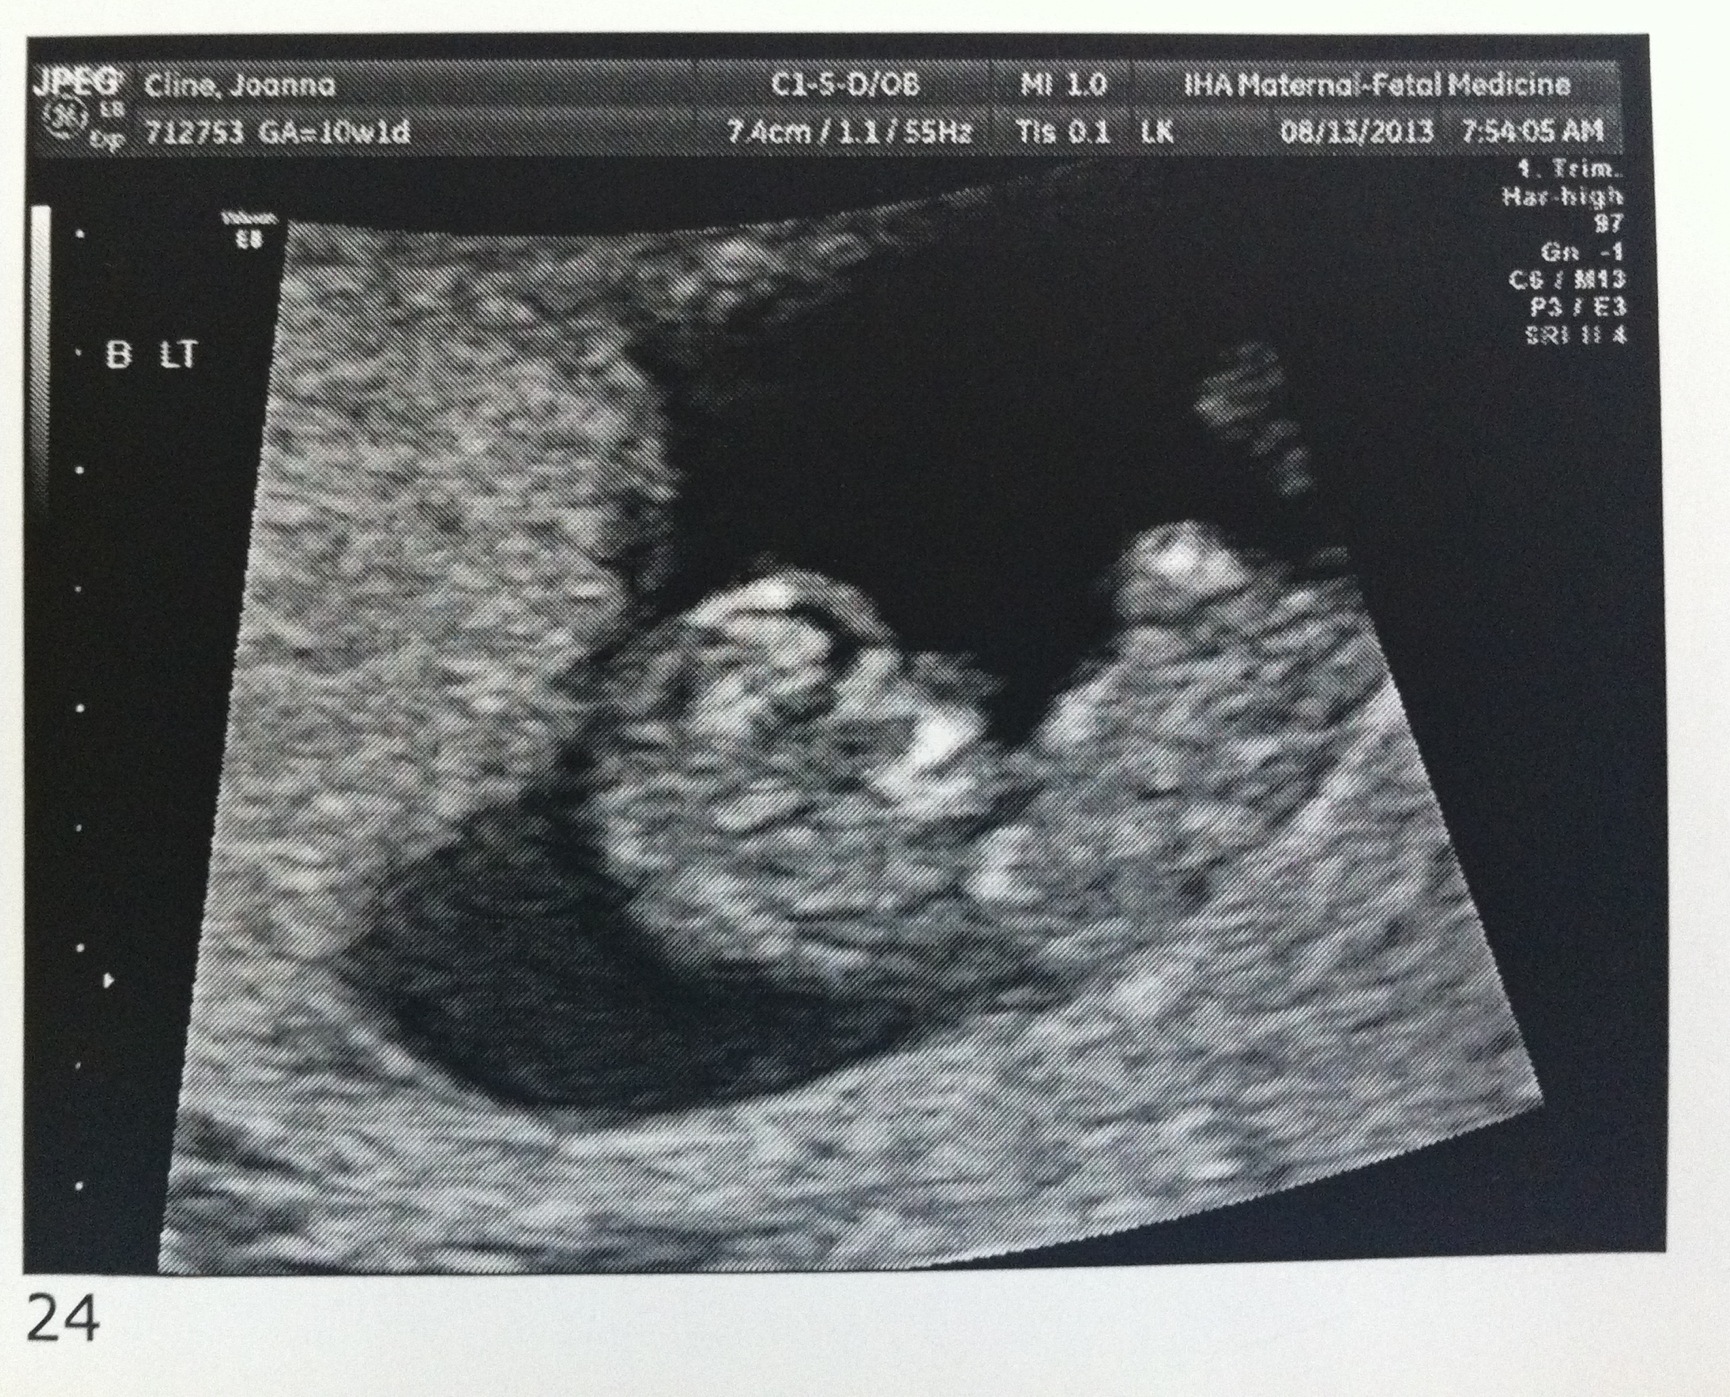

Good morning! I’m 10w1d today and we went for another ultrasound this morning. The u/s tech told us that everything looks exactly as she’d want it to at this point in the pregnancy. The heartbeats are great and they are wiggling around in there!

I’ve attached a few new photos – close ups of each and one group shot. 🙂